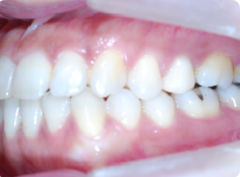

歯周病が進行し、グラグラして物が嚙めず、抜歯してインプラントにしていくことに。

インプラントはストローマンを使用、上部構造はジルコニアセラミックス

費用は2本で総額40万円(税込44万円)(他院の相場だと税込88万円位です)